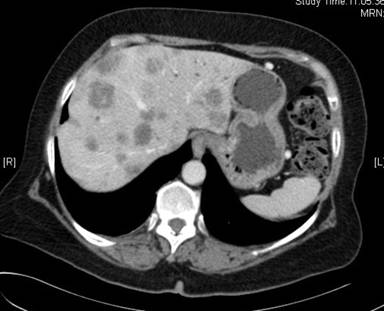

In January 2011 a 69-year-old female patient was admitted to our hospital due to persisting abdominal pain and elevated liver enzymes in the serum. Based on CT-scans (Figures 1 and 2) and laboratory diagnostics, adenocarcinoma of the pancreatic tail with multiple liver metastases was diagnosed. This diagnosis was confirmed histologically by biopsy of one of the liver metastases revealing poorly differentiated adenocarcinoma (Figure 3). Because of the clear constellation of diagnostic findings immunohistochemistry was dispensable. In our interdisciplinary tumor conference palliative chemotherapy was suggested. Because of the patients’ excellent performance status (ECOG 0) a first line therapy including folic acid, fluorouracil, oxaliplatin and irinotecan (FOLFIRINOX) was initiated in February 2011. In follow up staging CT scans showed significant shrinkage of the liver metastases and of the primary tumor, while serum CA 19-9 decreased concomitantly (Figure 4). After 2 years of chemotherapy, in February 2013, liver metastases could hardly be detected anymore, whereas the primary tumor in the pancreatic tail was still detectable and suspicious of residual cancer tissue. Thus, chemotherapy with FOLFIRINOX was continued. Subsequently, the lesion in the pancreatic tail stayed exactly the same size over another year of chemotherapy, while liver metastases did not recur as long as FOLFIRINOX was administered. In April 2014 we additionally performed an FDG-PET-CT-scan to find out whether the primary lesion in the pancreatic tail was still representing vital tumor tissue. Neither in the liver nor in the pancreatic tail FDG-uptake was increased (Figures 5, 6). Thus, we paused chemotherapy for 12 weeks and performed another CT-scan in August 2014 revealing a single metastasis in segment IVb of the liver. This metastasis was treated by radio frequency ablation (RFA). Six weeks later another CT-scan showed no sign of vital tumor tissue in the pancreas or the liver or elsewhere in our patient.

Figure 2. CT-scan of our patient in February 2011: several metastases in both lobes of the liver. |